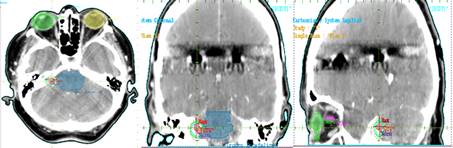

Se realizó una técnica con isocentro único con 6 arcos no coplanares con colimación del haz con Sistema de Conos. Se seleccionaron conos de 18 mm. El procedimiento se realizó en un Acelerador Lineal Varian Clinac 600 Figura 3

La lesión fue cubierta por la curva de isodosis de 80% normalizada en 12 Gy. Se obtuvieron puntos de máxima dosis de 15,03 Gy dentro del GTV y la lesión recibió un promedio de 14,28 Gy; la cóclea, principal OAR, recibió una dosis máxima de 7,09 GY. Figura 4.

Estos parámetros son estudiados en el histograma dosis volumen (DVH por sus siglas en inglés Dose-Volume Histogram) Figura 5.